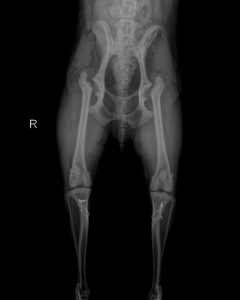

犬膝关节病变矫正手术

犬膝关节病变在临床上越来越常见。易发犬种中,最多见的是小型贵宾犬,卷毛比熊犬,迷你杜宾,京叭等。发病后,有一个最直观的现象,我们可以观察得到,患肢蜷缩,呈三脚跳姿势。

外科手术纠正是解决膝关节病变的一个途径。比如,髌骨内翻,外翻,前十字韧带断裂者。随着临床病例的增加和医生技能提高,手术变得越来越成熟。术后成功率也越来越高。

但是,以髌骨脱位为例,在什么情况下,我们需要做韧带重叠术,什么情况下,我们又需要做滑车再造成形术,甚至是胫骨结节移位术,这里边有着巨大的学问。

我们首先需要掌握的是髌骨脱位的分级。一般是四级。很多教科书和医生的博客里都介绍到了,这里不做过多的重复了。医生根据不同的等级情况来确定动物是否手术,并选择哪种手术。但是有一个问题,髌骨脱位的分级难以界定。每一个分级之间的差距是细微的。这一点在很大程度上影响了医生对动物病情的判断。

有。我们可以用另外一个途径来面对这个问题—Q角。

Q角(quadriceps-angle)  [ˈkwɔ:driseps] 书面语叫股四头肌夹角。它指髂前上棘至髌骨中心点连线与髌骨中心至胫骨结节中心连线所形成的夹角。正常Q角动物约为10°~15°(人的应该在5°~10°)。若Q角大于15°则股四头肌收缩时产生使髌骨向外移动的分力。随着Q角的增大向外侧牵拉髌骨的分力逐渐增大,髌骨稳定性也越来越差。加之在剧烈运动过程中的不确定力,髌骨可游离出滑车沟。所以髌骨脱位很容易发生。

4、截骨矫形术

如果病犬通过以上方法无效及同时膝关节严重畸形,应实施截骨矫形术,将股骨远端截断,纠正成角,使膝关节与髋关节和跗关节恢复成一条轴线上。